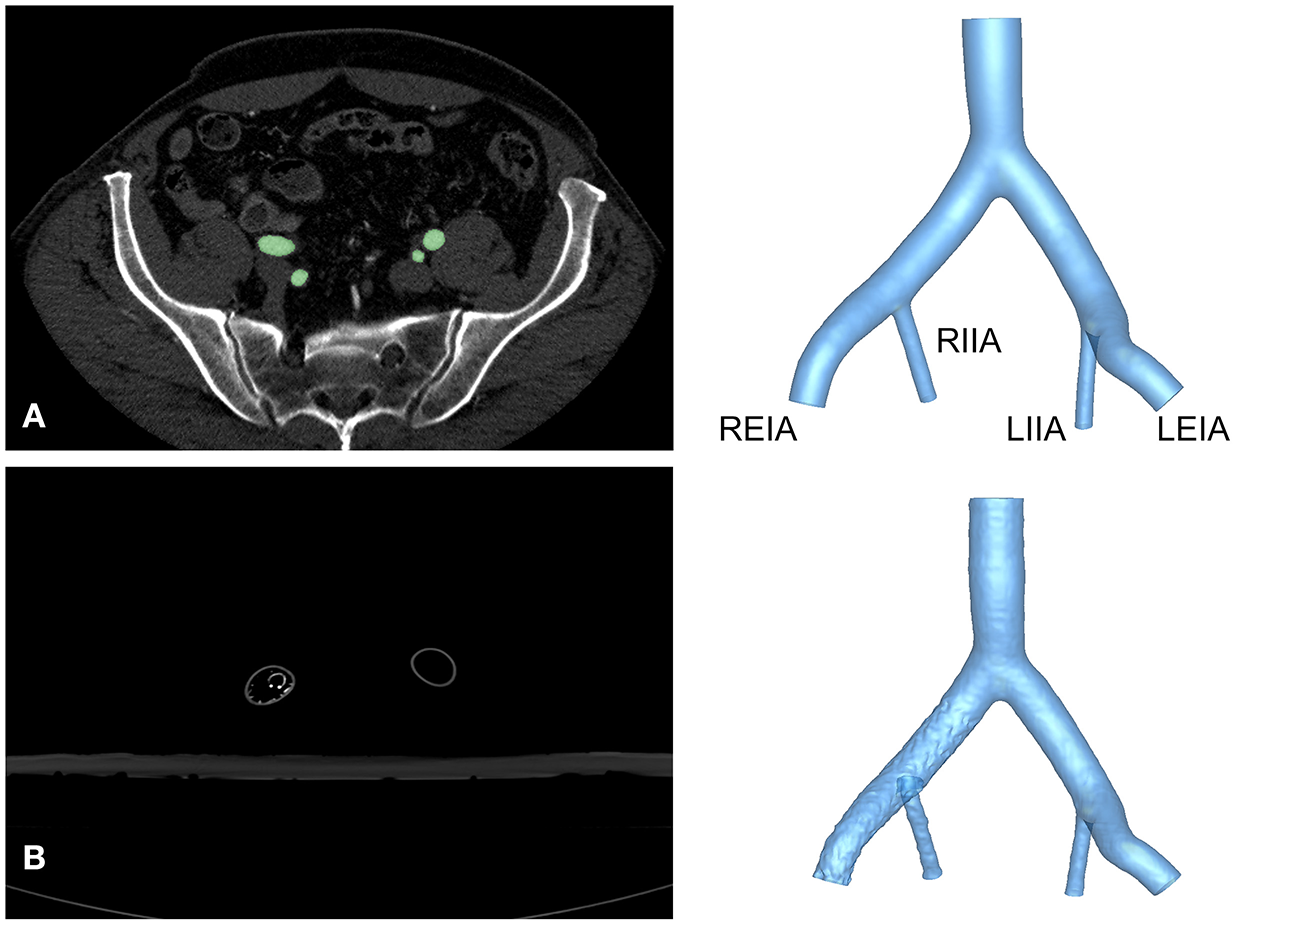

This study was approved by the Institutional Review Board of the Chinese PLA General Hospital (S201703601). All subjects provided written informed consent. The anatomy of the iliac artery was assessed in subjects with abdominal pain, and arterial disease was ruled out by computed tomography angiography (CTA) using a 16-detector row scanner (Aquilion 16® Toshiba Medical Systems, Japan), as shown in Figure 1. A semi-automatic, threshold-based segmentation tool (Mimics 19.0; Materialize, Belgium) was used to reconstruct the iliac artery model. Then, the iliac artery model was modified by referring to the anatomical characteristics of Chinese patients to obtain a model that was representative of the anatomy of this population. The anatomical size of the iliac artery was shown in Table 1. Three-dimensional (3D) printing software (Magics 19.0; Materialize, Belgium) and computer-aided design software (Solidworks 2018; Dassault Systems, Massachusetts, USA) were used to attain the finial iliac artery model. The anatomical parameters were also shown in Table 1.

Figure 1

Reconstruction of the iliac artery model. (A) Axial view of CTA images from a healthy volunteer and reconstructed structure of Model A. (B) Axial view of CTA images and reconstruction of Model B. LEIA, left external iliac artery; LIIA, left internal iliac artery; REIA, right external iliac artery; RIIA, right internal iliac artery.